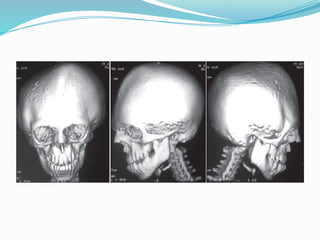

3D CT

Anterior View

Nasofrontal suture

Zygomaticofrontal suture

Zygomaticotemporal suture

Left Lateral View